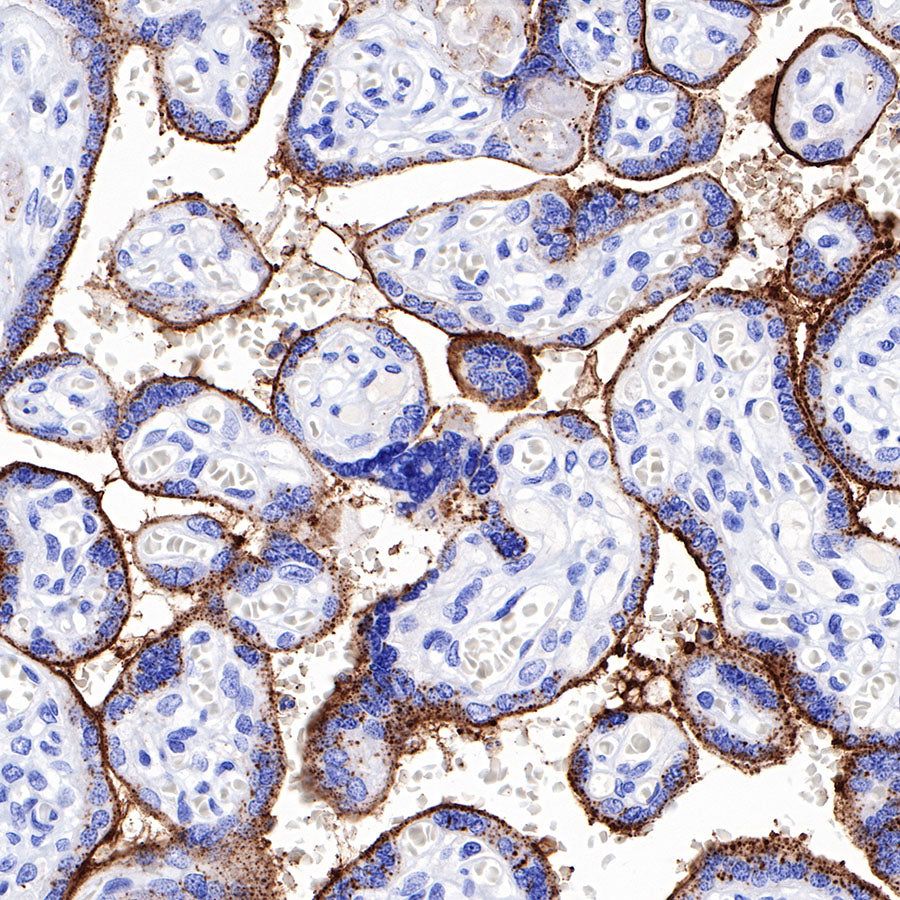

Syndecan-1 (CD138) is mostly restricted to epithelia, and bears heparan sulfate chains that are capable of interacting with a large array of polypeptides, including extracellular matrix components and potent mediators of proliferation, adhesion and migration. For this reason, it has been studied extensively with respect to carcinomas and tumor progression. Frequently, but not always, syndecan-1 levels decrease as tumor grade, stage and invasiveness and dedifferentiation increase. However, in some tumors, levels of syndecan-1 increase, but the characterization of its distribution is relevant. There can be loss of membrane staining, but acquisition of cytoplasmic and/or nuclear staining that is abnormal. Moreover, the appearance of syndecan-1 in the tumor stroma, either associated with its cellular component or the collagenous matrix, is nearly always a sign of poor prognosis [PMID: 33921767].

Picture

Immunohistochemistry